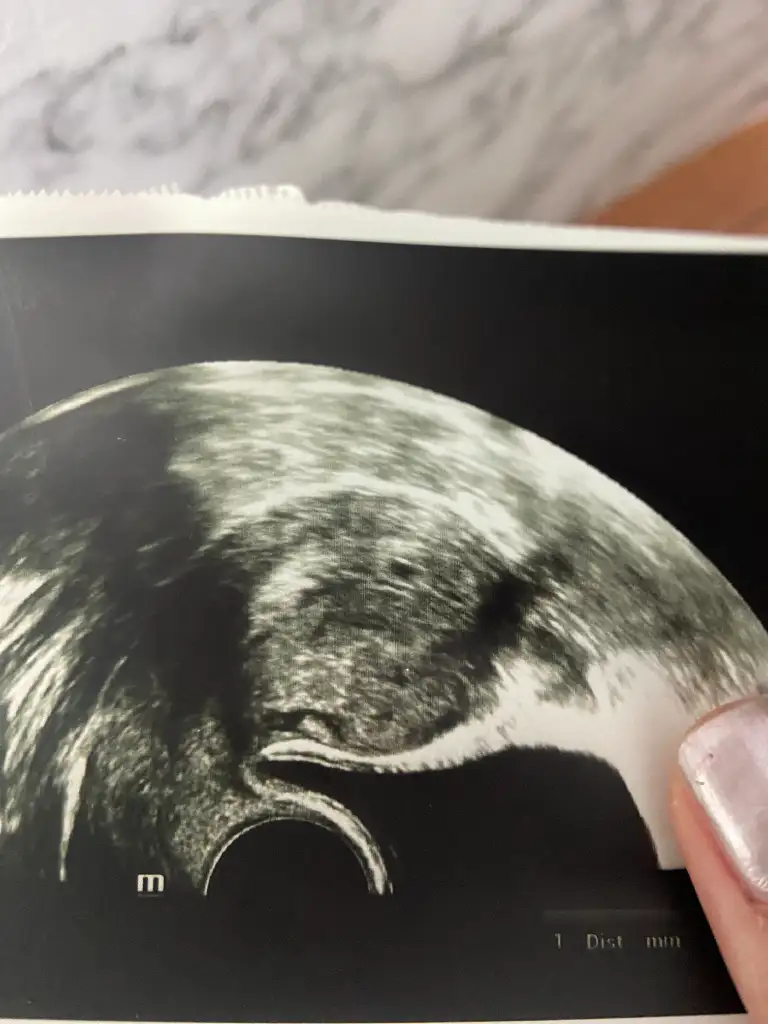

Aaa öyle mi hesaplamıyor tüp bebekte farklı değil mi kuzu. Gördüm gördüm allaha şükür 3 mm miş minik tanemiz 🥹 bayramdan önceye muhtemeln yetişmez de 10 haziranda kalp atışı için gelirsiniz dedi doktorum ilaçlars aynen devamm

• IMG_7457.webp

IMG_7457.webp

28,7 KB · Görüntüleme: 31